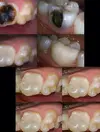

Diş Çürükleri

Zirkonyum uygulamalar

Porselen uygulamaları